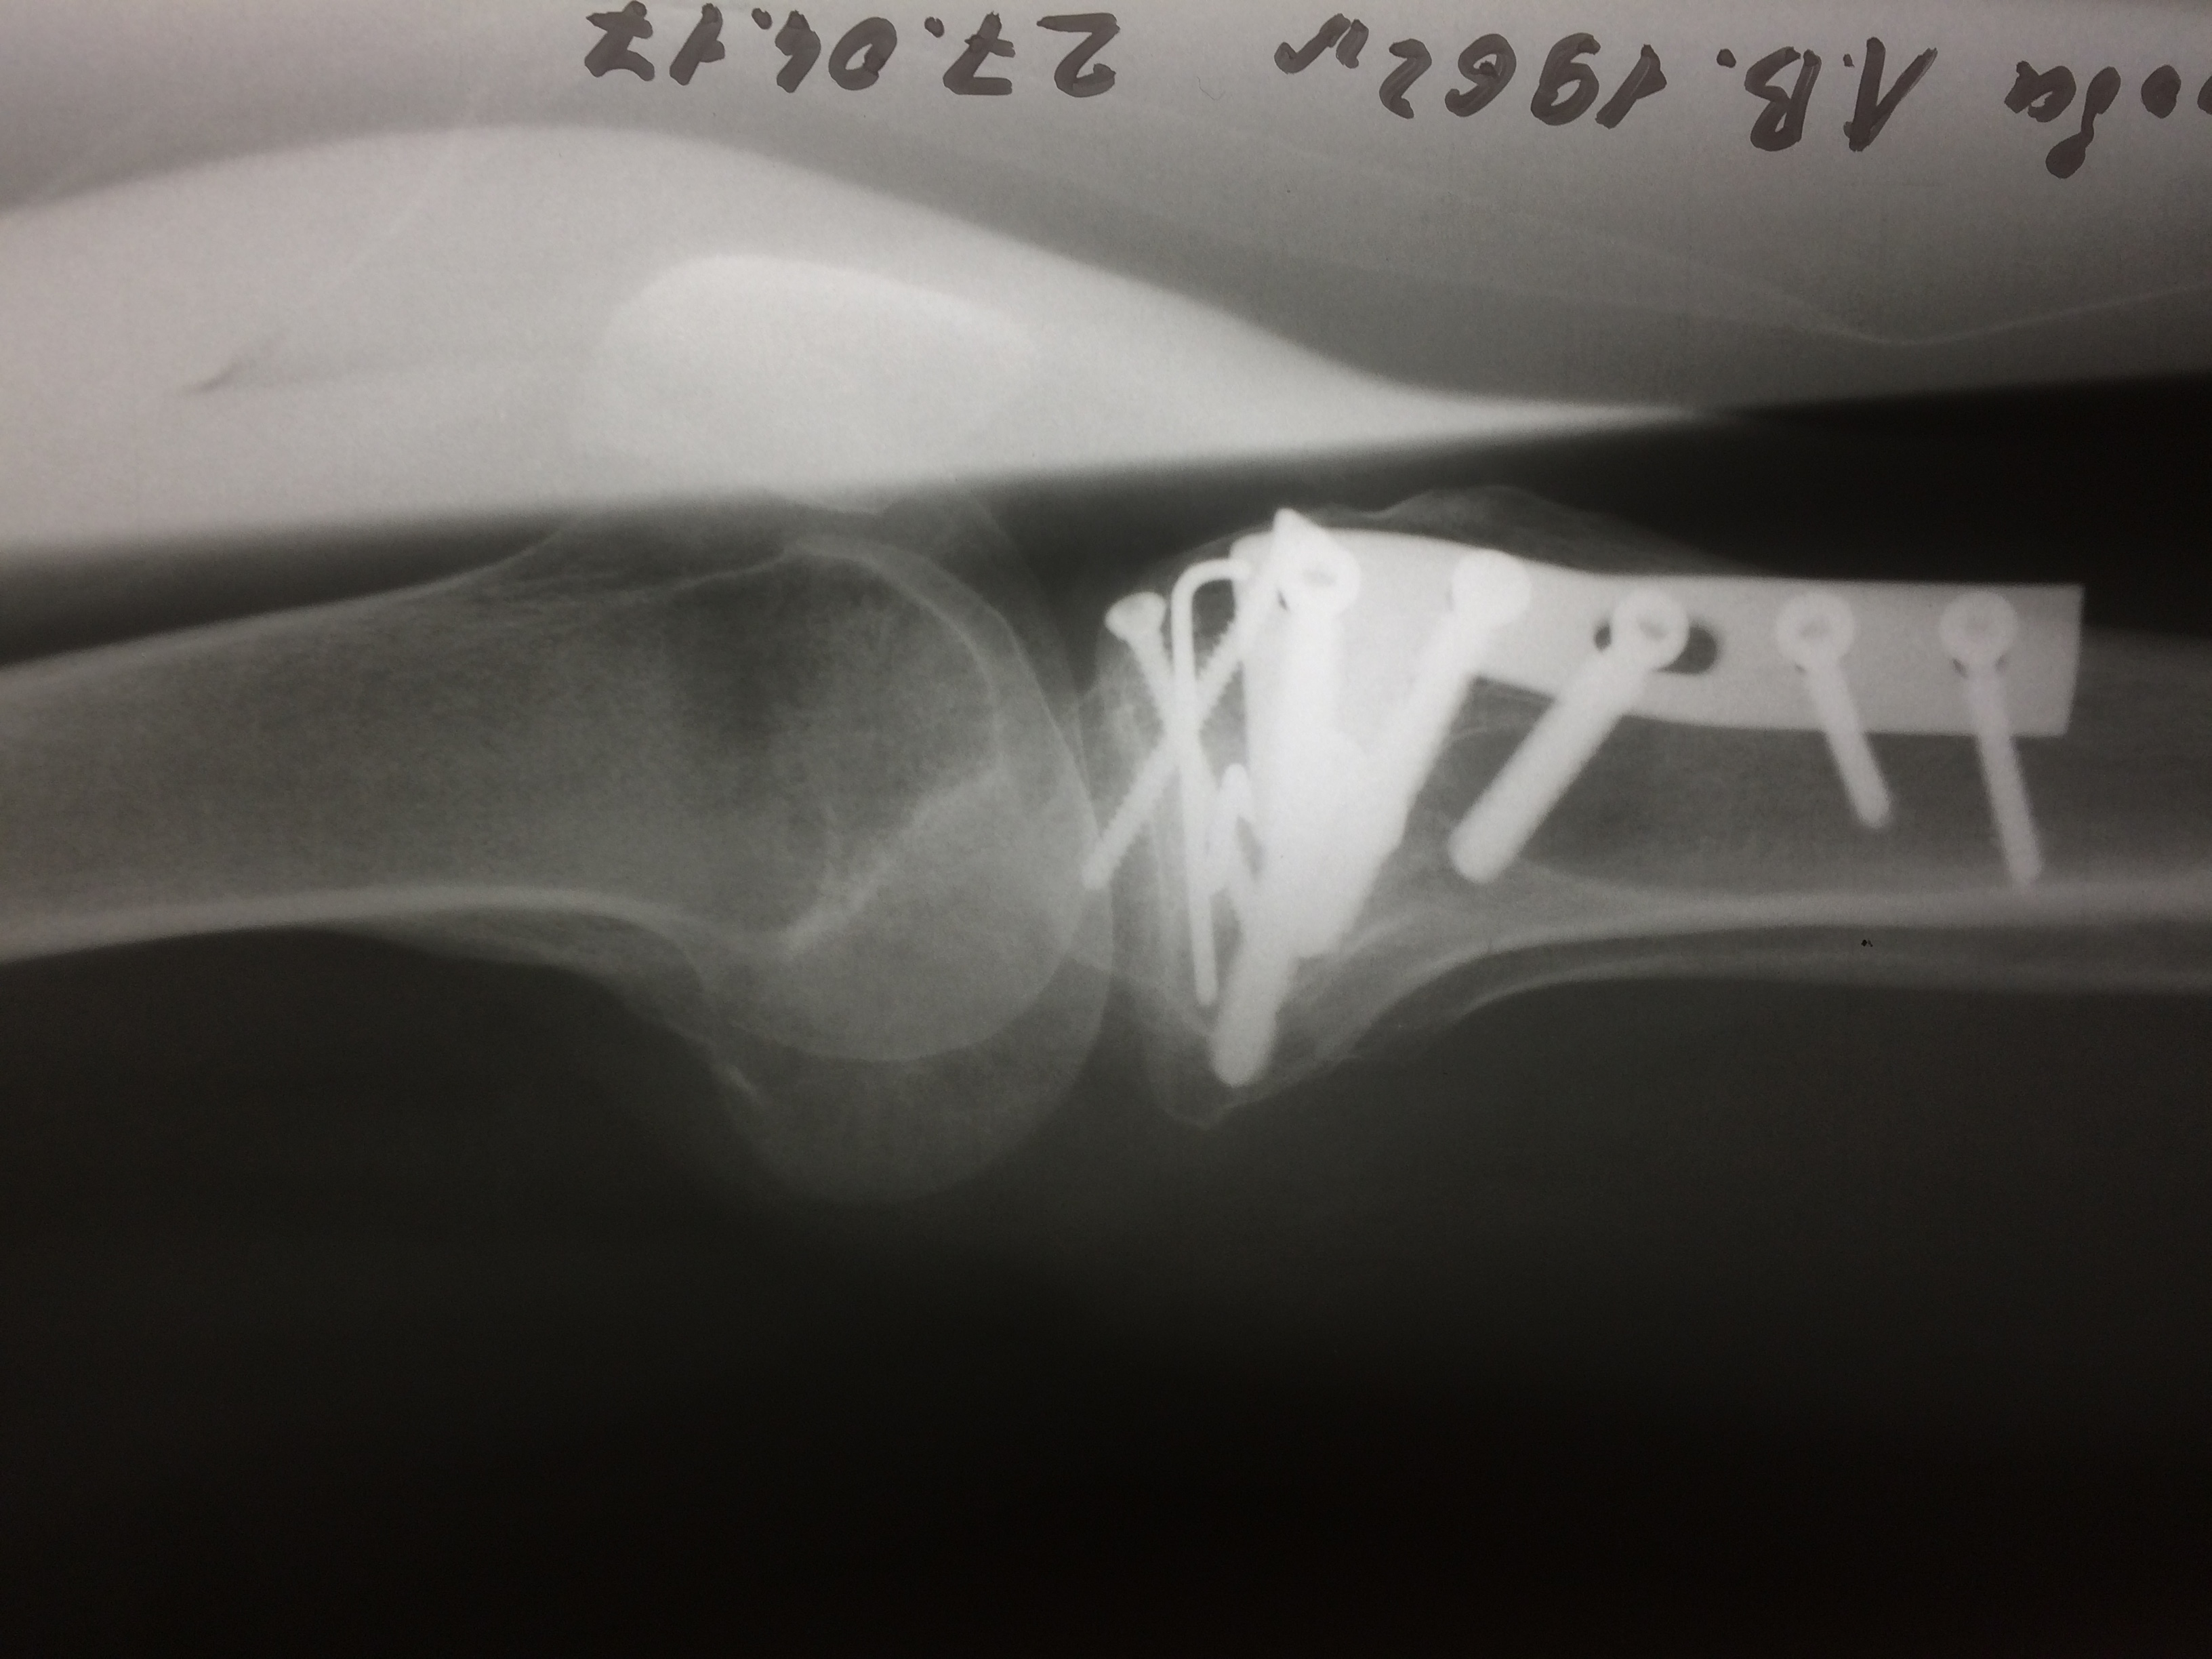

Использование материала Остеоматрикс при импрессионном оскольчатом переломе наружного мыщелка большеберцовой кости по типу Schatzker II

Использование материала Остеоматрикс при импрессионном оскольчатом переломе наружного мыщелка большеберцовой кости по типу Schatzker II.

Операция - открытая репозиция, остеосинтез большеберцовой кости опорной пластиной с костной ксенопластикой маетриалом "Остеоматрикс". На контрольных снимках в три и шесть месяцев имеется консолидация перелома, миграции фиксатора нет, имеется остеоинтеграция ксенопластического материала. Функция коленного сустава полная.

Отдаленные результаты через 6 (шесть) месяцев